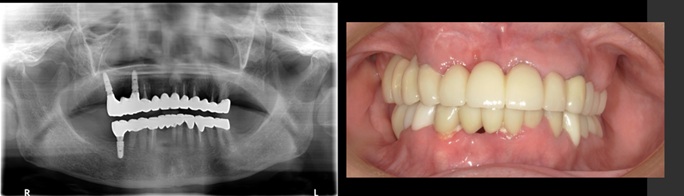

インプラント6本埋入+FGG(60代女性)

治療前

治療後

施術名 | インプラント6本埋入+FGG |

---|---|

主訴 | 噛めない |

施術の副作用(リスク) | 脱落感染 |

施術の価格 | 施術の費用 1本GBR5万~10万(税抜き)+インプラント埋入補綴まで35万(税抜き) |

コメント | 下の前歯は再生療法ブリッジを行い歯を保存しました |